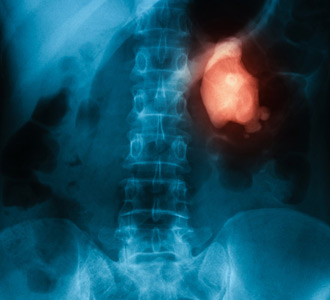

Kidney stones vary in size. Some are like fine grains of sand, while others are about the size of golf balls.

Linked to invasive bladder cancer, ureter cancer has a tendency to spread to nearby areas.